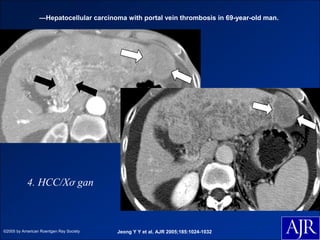

—Small hepatocellular carcinoma on dynamic contrast-enhanced CT in 49-year-old man.

4. HCC/Xơ gan

©2005 by American Roentgen Ray Society   Jeong Y Y et al. AJR 2005;185:1024-1032

—Hepatocellular carcinoma with portal vein thrombosis in 69-year-old man.

Chiến lược chẩn đoán

Việc phát hiện tổn thương HCC/Xơ gan sẽ làm thay đổi hoàn toàn

tiên lượng và góp phần quan trọng trong xác định chiến lược điều trị.

- Theo dõi siêu âm 6-12 tháng / 1 lần hoặc ít hơn.

- Nếu có tổn thương:

+ <2cm (Biopsy(-) thì theo dõi tiếp).

+ >2cm (Washout trên CLVT hoặc CHT)

- Nếu biến chứng HCC: RF – Hóa chất – Phẫu thuật.

• #90 — Hepatocellular carcinoma with portal vein thrombosis in 69-year-old man. Arterial phase CT scan shows low-attenuating mass (white arrows) in lateral segment of left hepatic lobe. There is heterogeneous enhancing lesion (black arrows) within left portal vein. Cirrhosis and ascites are seen.